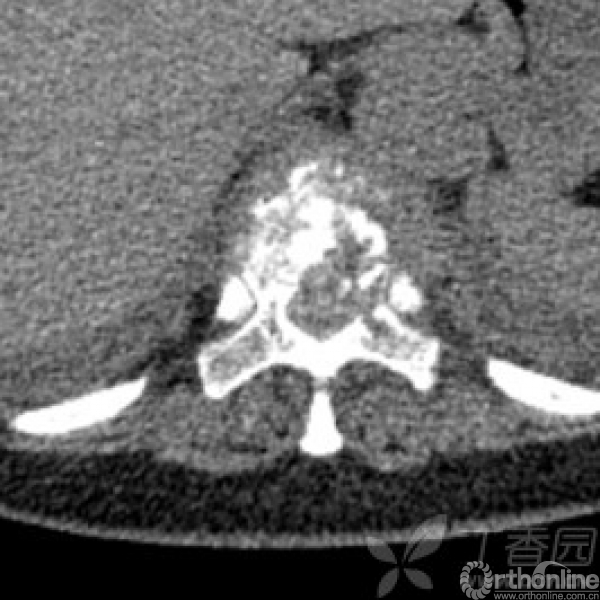

胸椎多椎体病变,如果诊断和治疗?